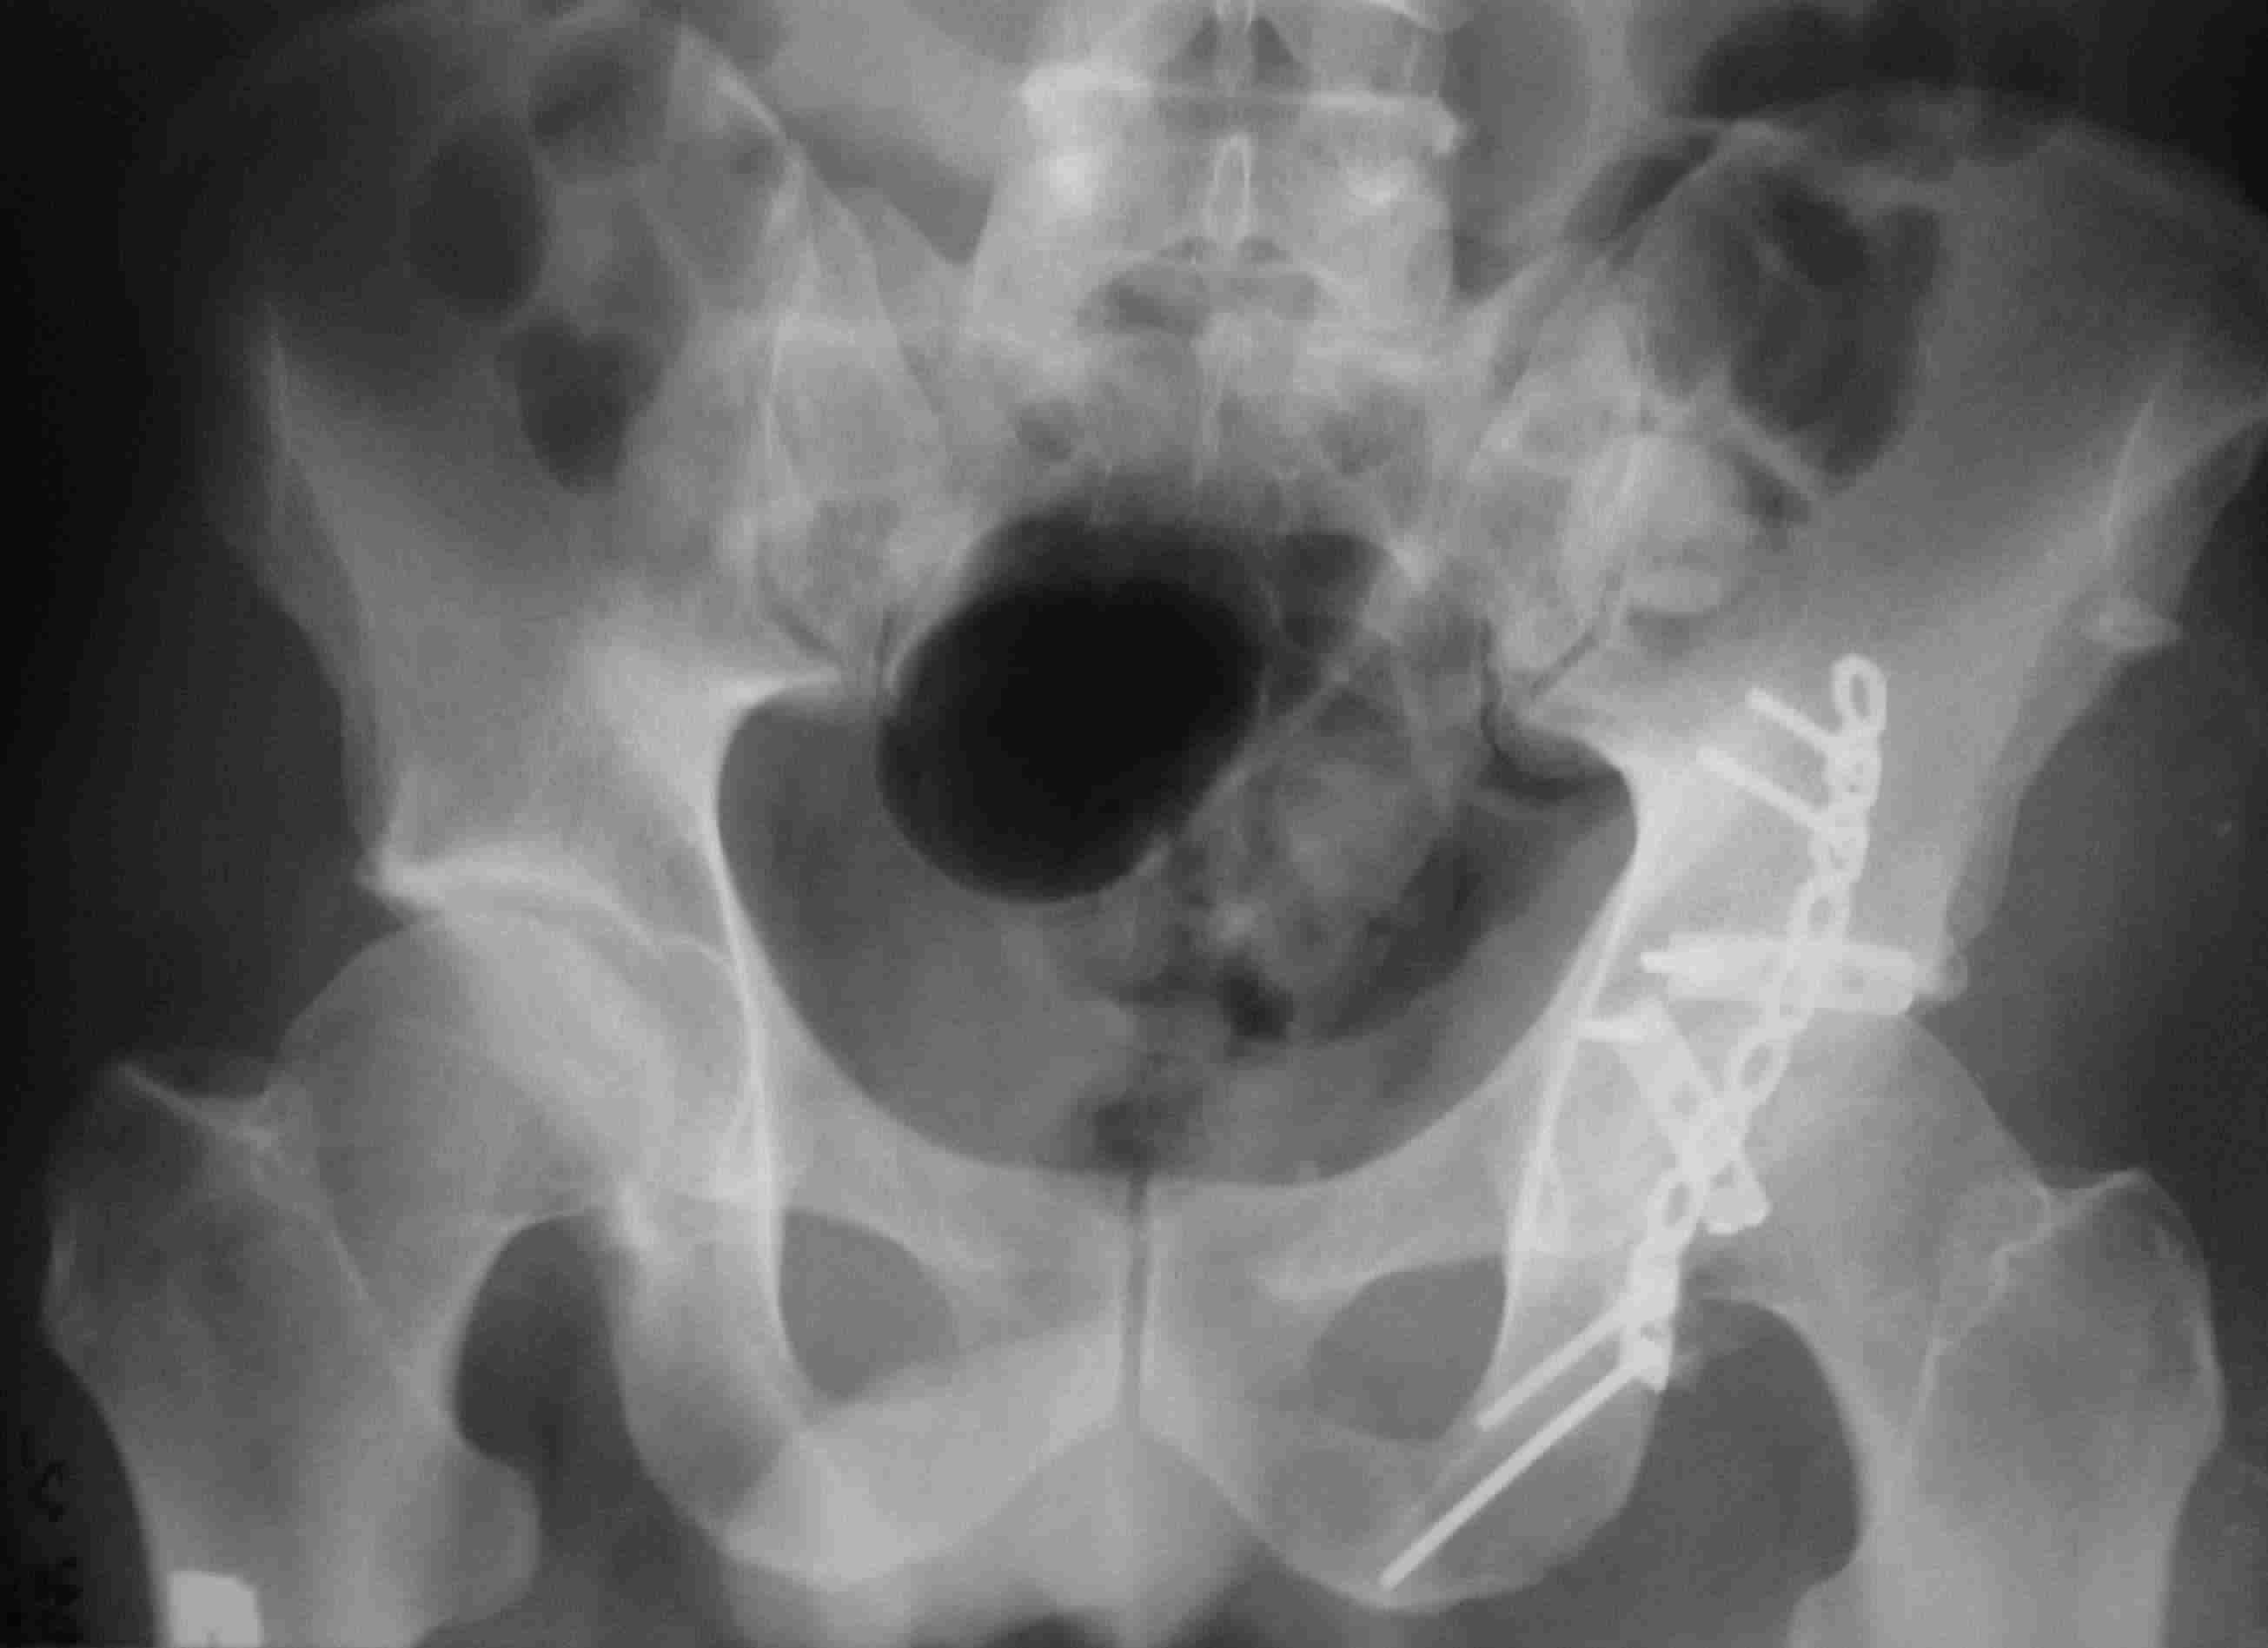

[Ortho] перелом проксимальной тибии + вывих бедра

Серия КТ сканов в аппарате